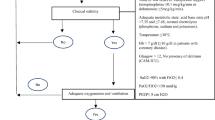

In this IRB-approved study, a waiver of informed consent was granted to record breathing pattern and related data in 97 adults (Table 1) in a surgical ICU at a university medical center who were considered candidates for extubation based on routinely used inclusion and exclusion criteria (Table 2). Patients had received ventilatory support for 9 ± 3 days (Model 840 ventilator, Puritan Bennett, Pleasanton, CA). The first 38 or approximately 40% of patients were designated as a training set to determine threshold values for indices that best differentiated patients who were successfully extubated (n = 31) or who failed extubation (n = 7), a 22% failure rate. The predictive power of the threshold values for each index was assessed in the subsequent 59 or 60% of patients in a prospective validation set who were successfully extubated (n = 47) or who failed extubation (n = 12), a 25% failure rate. The reported incidence of extubation failure ranges between 6 and 47% [14]. Failure rates for our two patient sets are comparable and near the middle of this range.

As routinely used, a spontaneous breathing trial (SBT) of PSV 5 cmH20 with PEEP 5 cmH2O (FIO2 ≤ 0.40) was performed with sedation/analgesia temporarily removed or reduced to obtain a Riker Sedation-Agitation Score of 4 [15]. During the SBT all indices were measured after 30 and 90 min; measurements at 90 min were used for statistical analysis. An arterial blood gas was obtained 5 min prior to and 30 min after extubation. The decision to extubate was made by the attending physician based on routinely used criteria (Table 2). For both patient sets and during all phases of the study, WOBN/min data were blinded to attending physicians and did not influence the decision to extubate. Following extubation, all patients breathed spontaneously through an aerosol facemask (FIO2 0.40). Successful extubation was defined using routine standards as the ability to sustain appropriate spontaneous breathing (f ≤ 30/min) and blood gas exchange, i.e., pulse oximeter oxygen saturation (SpO2) > 92%, PaO2/FIO2 ≥ 150–300, PaCO2 ≤ 50 mmHg for non-chronic obstructive pulmonary disease (COPD) patients, ≤55–60 mmHg for COPD patients, pH ≥ 7.30, and ability to cough and protect airway for greater than 24 h after extubation. Objective criteria for extubation failure were PaCO2 > 50 mmHg for non-COPD patients and >55–60 mmHg for COPD patients, PaO2 < 60 mmHg (FIO2 ≤ 0.40), f > 35/min, inability to cough and/or protect airway, and a worsening of hemodynamic or neurological conditions. Patients failing extubation were reintubated and provided with ventilatory support at the direction of the attending physician.

For the training set, threshold values of 11 indices were identified (Table 3). Nine were indices used traditionally for assessing readiness for extubation including f, V T, f/V T ratio, MV, PaO2/FIO2 ratio, SaO2, PaCO2, V D/V T ratio, and Crs. The two remaining indices were WOBN/min and VCO2. For example, the threshold value identified for WOBN/min was ≤10 J/min.